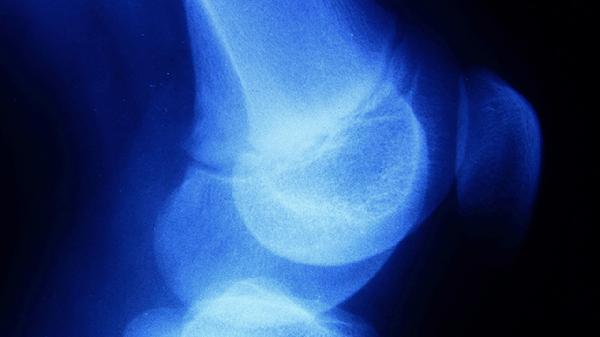

跟骨骨膜炎通常可遵医嘱使用布洛芬缓释胶囊、塞来昔布胶囊、阿司匹林肠溶片、双氯芬酸钠缓释片、盐酸氨基葡萄糖胶囊等药物。跟骨骨膜炎可能与慢性劳损、感染、创伤等因素有关,表现为足跟部疼痛、肿胀、活动受限等症状。